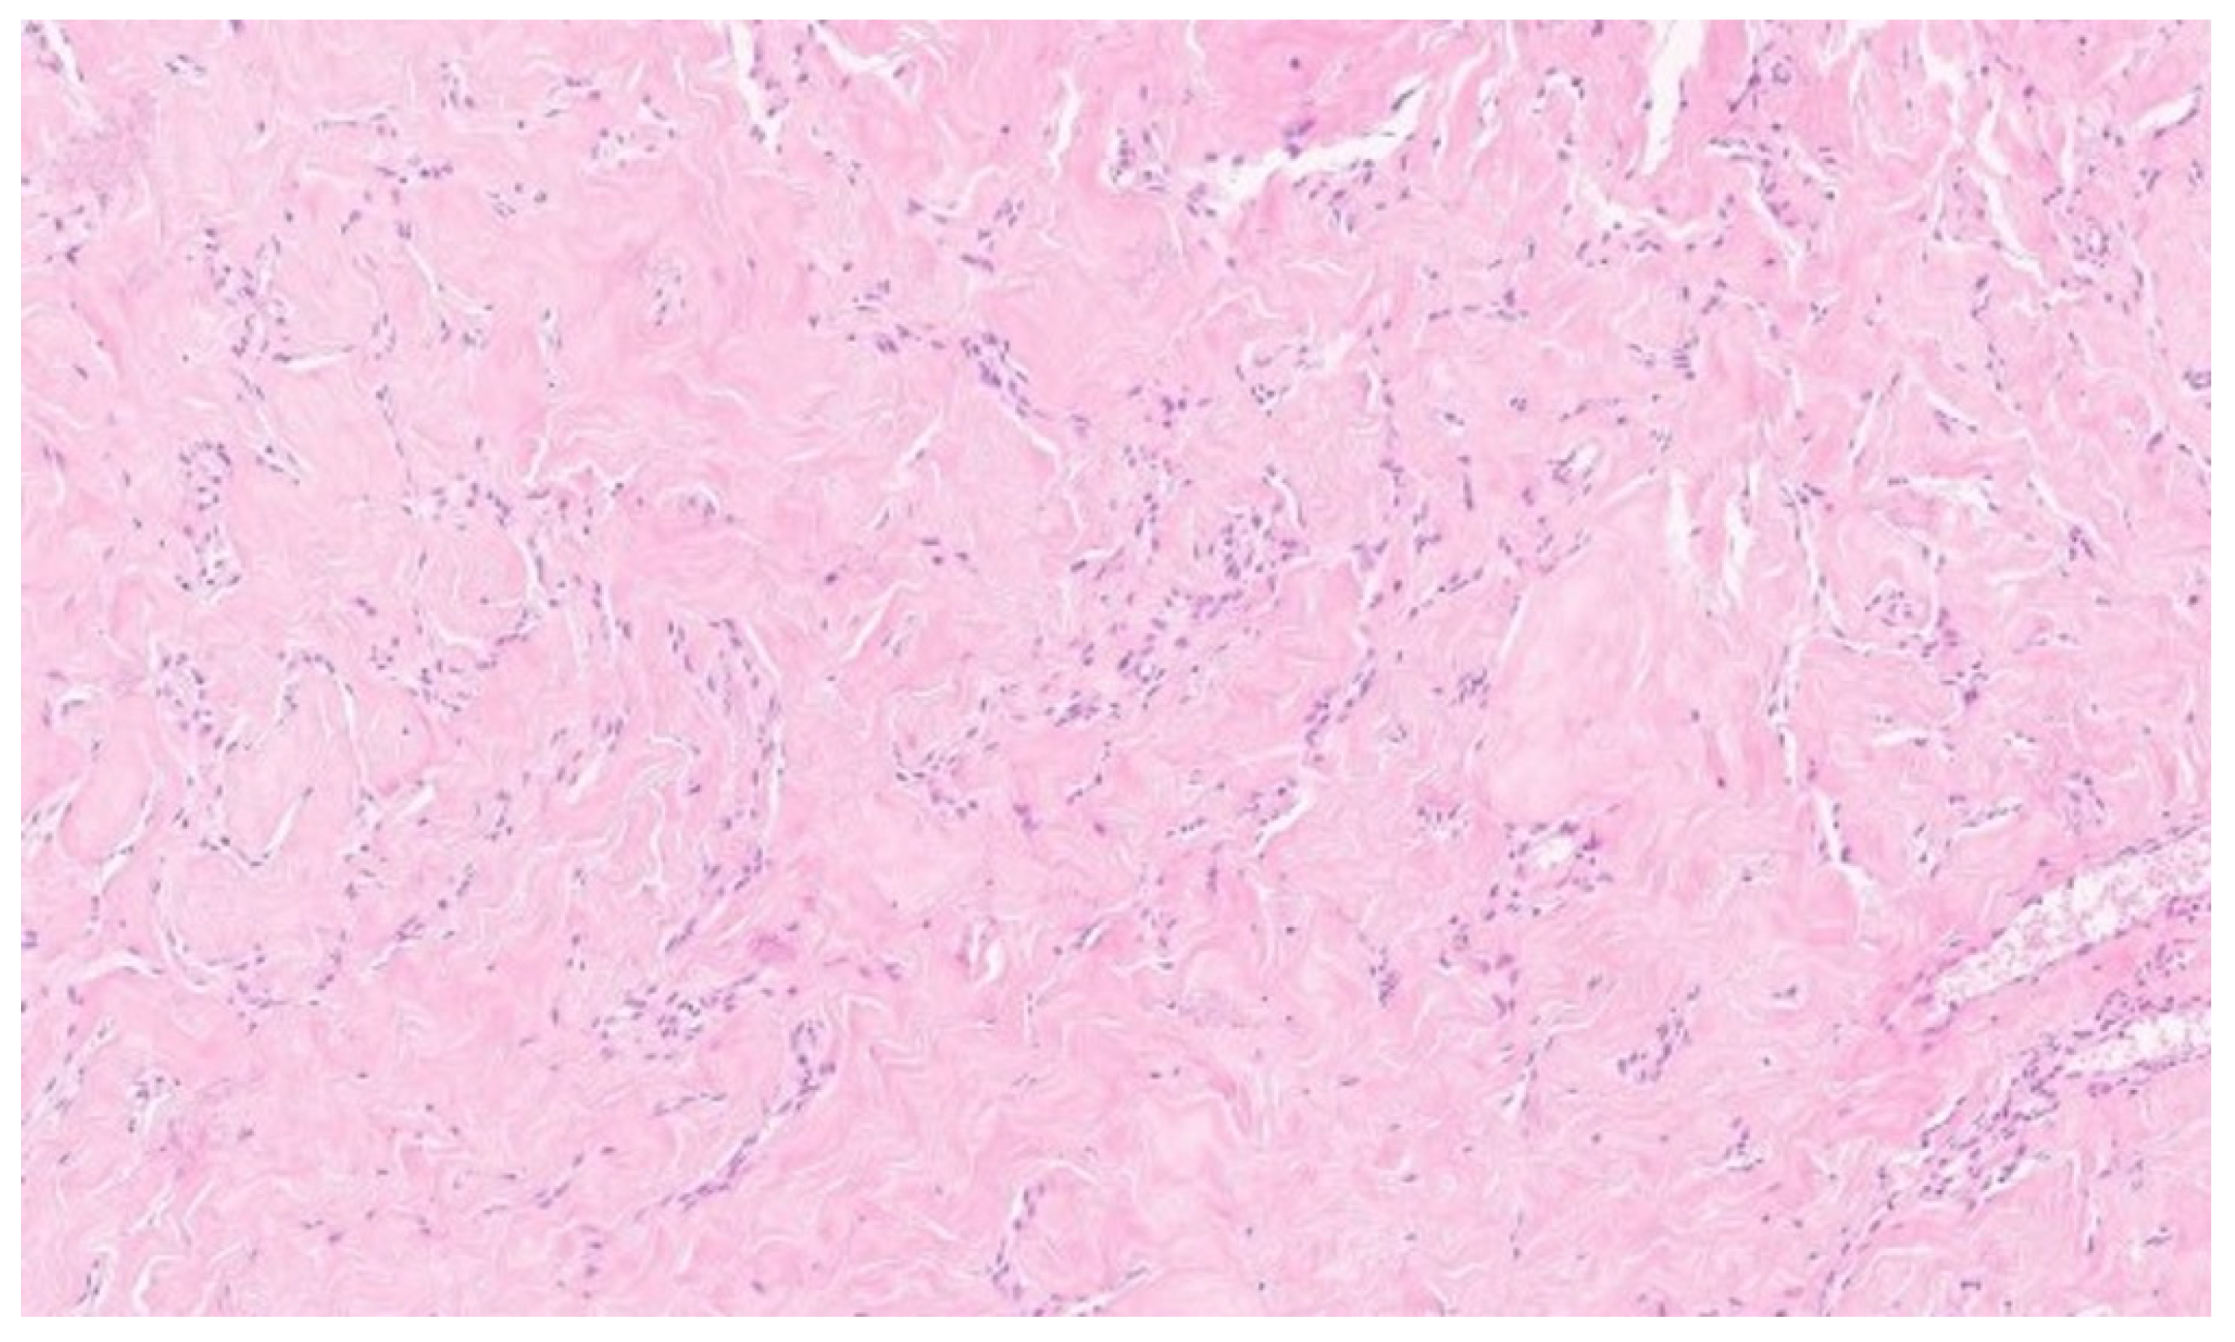

Due to the size of the lesion, diagnostic evaluation was extended to include magnetic resonance imaging (MRI). MRI confirmed the previous findings, showing a well-circumscribed lesion without diffusion restriction. No additional focal pathological changes were detected. No pathological lymph nodes were visualized in either axilla (levels I, II, or III). MRI was classified as BI-RADS category 4 for the left breast and category 1 for the right breast (Figure 1).

Figure 1. Magnetic resonance imaging of the left breast. Axial T1-weighted contrast-enhanced sequence reveals a large, homogeneous tumorous lesion, indicated by white arrows.

The histopathological examination confirmed the diagnosis of pseudoangiomatous stromal hyperplasia (PASH). The specimen was described as a solid, light gray-to-yellow tumor measuring 11 × 10 × 4.8 cm3, with the capsule preserved and intact (Figure 2 and Figure 3).

On gross examination, PASH typically appears as a well-circumscribed and encapsulated breast lesion, occasionally presenting in a diffuse form. The cut surface is smooth, firm, or rubbery, glistening, and varies in color from gray to tan-pink, yellow, or white [4]. In our patient, the lesion was described as a solid, light gray–yellow mass.

Microscopically, the hallmark of PASH is the presence of slit-like spaces resembling vascular channels, lined by spindle cells, without endothelial markers (CD31–), but with positive CD34 expression, which was also confirmed in our case [4,16].